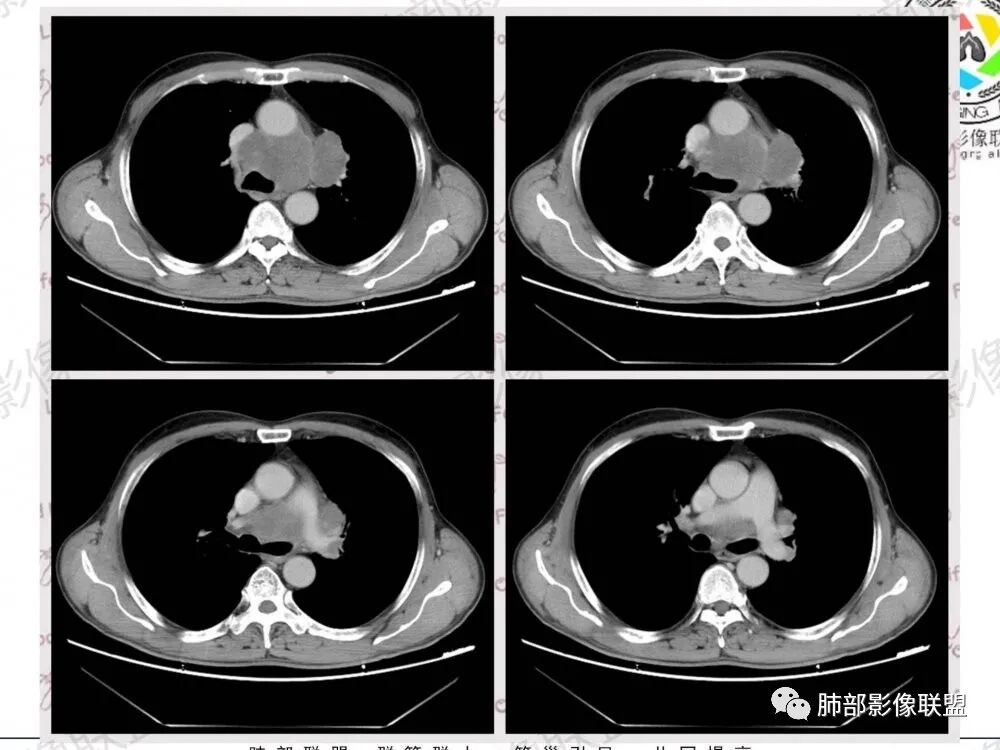

57岁男性,长期吸烟史,有血吸虫病史,有粉尘接触史。发现纵隔淋巴结肿大2年,声嘶伴咳嗽咳痰半月。两年前胸部CT见左上肺尖后段结节并肺门淋巴结肿大,治疗后左上肺结节消失。目前胸部CT:肺气肿,左上肺尖后段见条索影(原来结节治疗后的改变?),肺门、纵隔淋巴结肿大并融合,似见薄壁包膜样强化。考虑淋巴结结核可能性大,注意鉴别淋巴瘤、转移、结节病等。

男性,57岁,发现纵膈淋巴结肿大,现声嘶伴咳嗽咳痰。COPD背景,纵隔内、左肺门多发肿大淋巴结相互融合,冰冻纵隔?增强后轻度强化,主气管向右侧推移。考虑肺癌,小。

左上肺门和左下肺门淋巴结,纵膈淋巴结肿大,融合明显。右肺门未见肿大淋巴结。上腔和邻近左上,下肺动脉推移受侵变细明显。先考虑恶性肿瘤的淋巴结转移。病理亚型不敢定了,前两天刚碰见一个这样的腺,先猜小细胞。既往结核粉尘吸入,淋巴瘤第二位吧。

病史两年,左肺病变治疗后有吸收,需要结合老片对比,有血吸虫,粉尘史,纵隔及肺门淋巴结肿大,淋巴结形态消失,部分融合,周围血管挤压,增强后环形强化,肺内可见多发肺气肿,左肺尖可见纤维索条影(可能既往有陈旧性结核),综合考虑:一元论:结核(纵隔淋巴结及左肺都是结核),二元论:肿瘤性病变合并左肺结核(纵隔淋巴瘤,如果是小细胞肺癌的这么大淋巴结,肺内病灶没有转移,有点奇怪)

中老年男性,长期吸烟,肺气肿明显,发现纵隔淋巴结两年了,声音嘶哑,病灶压迫喉返神经了?喉部有占位吗?左肺尖小片状病灶,周围多发长条纤维牵拉,胸膜增厚,纵隔及左肺门多发肿大淋巴结,增强后显示淋巴结融合且坏死明显,薄环状强化。如果是恶性肿瘤,小细胞癌或者鳞癌,肺内病变应该增大增多了;一元化我考虑纵隔淋巴结结核,左肺尖结核灶。

1.左肺门及纵隔见异常增大淋巴结,部分融合,不均匀轻度强化,未见明显坏死。

肿大淋巴结与纵隔血管等结构“无缝”贴合。

2.纵隔增宽但依旧居中。

1.这应当是常见的小细胞肺癌的转移方式。

2、小细胞癌恶性程度高,发展迅速,转移发生早;常有纵隔淋巴结的明显增大融合(发生率达96.5%),呈“冰冻纵隔”,淋巴转移常为逐站的连续性转移;亦有血行转移,脑、肾上腺、肝、胰、骨髓等;转移灶常比原发灶大得多,即“娘小崽大”特点;

3、因其对血管、支气管破坏程度轻,故坏死相对较轻,极少出现空洞;小细胞肺癌支气管壁肥厚、管腔狭窄,但表面可有正常黏膜,除非狭窄非常严重,否则不会引起支气管刺激症状,故该症状对其早期诊断无意义;受累支气管末梢侧阻塞性炎症少。